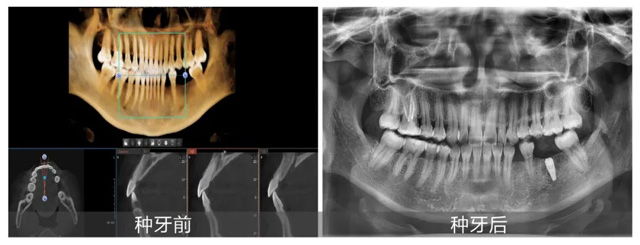

陸女士術前術后拍片對比

結合術后拍片結果,吳建方醫生對本次手術進行了簡單總結,現場觀眾們也紛紛利用和大咖面對面的機會,提出自己的疑問:“半口種牙需要多久?”“種植牙是一勞永逸的嗎?”吳醫生一一做了回答并表示:“非常高興能通過手術直播和答疑的方式,幫助顧客朋友們了解種植牙,這也促進了我和大家的充分了解與信任。希望大家都能用最適合自己的方式,重拾好口福!”